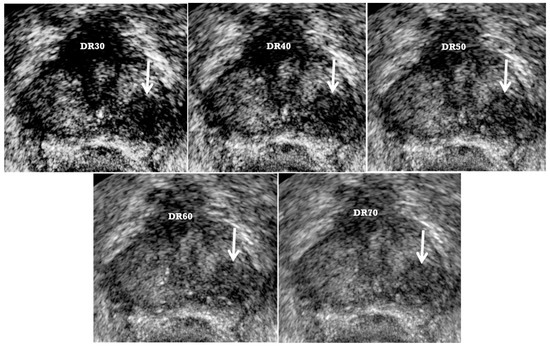

| TRUS Parameters | Old TRUS Techniques | New TRUS Techniques |

|---|---|---|

| US sequence | Harmonic imaging | Fundamental imaging |

| US artifacts | Rare | Frequent |

| Dynamic range | High | Low |

| Image resolution | High | Low |

| Tissue contrast | Low | High |